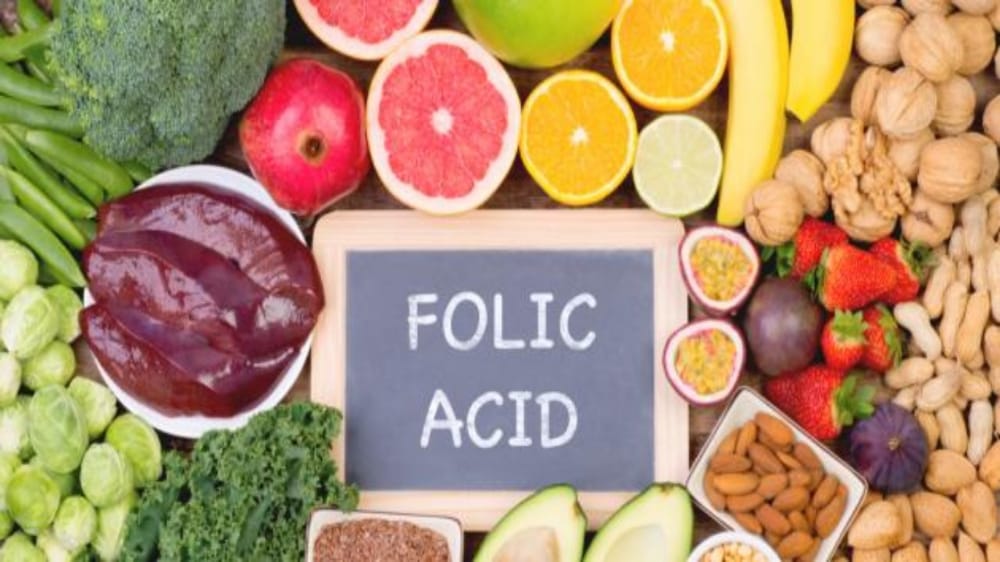

حمض الفوليك

استشارية: حمض الفوليك لا يمنع إسقاط الحمل

استشارية تكشف عن فيتامين يقلل تشوهات القناة العصبية للجنين

5 فواكه غنية بفيتامين “بي 9″ الضروري للحوامل

أهمية حمض الفوليك ومصادر الحصول عليه

“فهد الطبية” توضح مصادر حصول الجسم على حمض الفوليك

“الغذاء والدواء” توضح حقيقة فوائد إضافة حمض الفوليك للشامبو

دراسة: حمض الفوليك يقلل من خطر مرض التوحد الناجم عن المبيدات